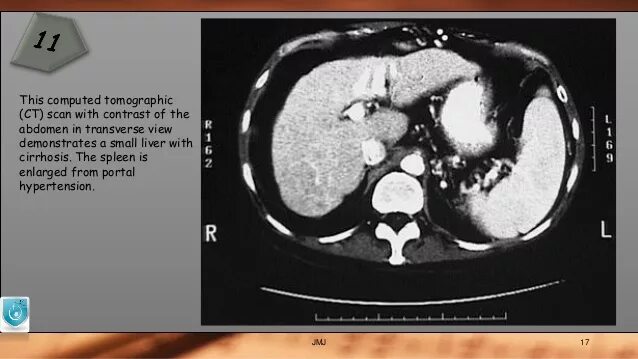

Фиброз кт